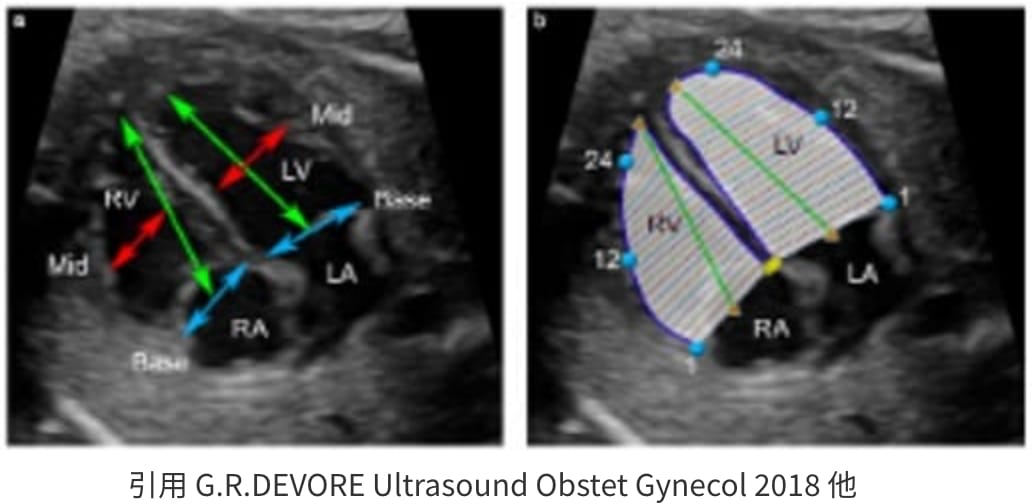

Fetal HQ

Fetal HQ®はSpeckle-Tracking法を用いて胎児心室壁の運動を解析する方法です。Speckle-Tracking法とは心筋の断層エコー画像上の小斑点(speckle)を追跡し心筋局所の機能を解析する方法で、成人の心臓超音波検査でも用いられています。一回数秒の動画の保存で複数の心機能が同時に評価できる新しい検査法です。

Fetal HQで測定できる項目

Sphericity index(SI)

心室の形態を定量化する。SIは四腔像における短軸径に対する長軸径の比率として表され、心尖部〜心基部を長軸に直交する24のsegmentに分け、segmentごとのSIを算出できる。1に近づくほど球形であると言える。

- 成人では心不全が増悪するほど心室内腔形が球形に近づく。

Fractional shortning

(拡張末期径−収縮末期径)/拡張末期径×100で表され、短軸で収縮能を評価する。SegmentごとにFSを算出できる。

Fractional area change

(拡張末期面積–収縮末期面積)/拡張末期面積×100で表され、面積で収縮能を評価する。

Global strain

(収縮末期心室内周長−拡張末期心室内周長)/拡張末期心室内周長×100で表され、心筋全体のストレイン(伸び縮み)を数値化することで心筋の三次元的な動きを評価する。

Fetal HQの臨床における活用はまだ限定的です。当院では先天性心疾患の胎児や、双胎間輸血症候群・胎児胸水・胎児貧血といった胎児治療が必要な胎児の心機能を評価するために、従来用いられている心機能の評価項目に加え、Fetal HQを用いて心エコー検査を行っています。データを積み上げ、Fetal HQの活用の幅を広げていきます。

胎児心不全の一例:著明な心拡大と収縮機能低下を認める